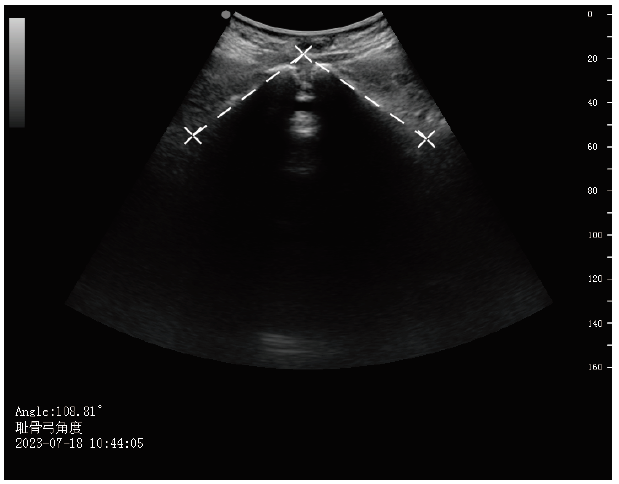

在产妇孕晚期常规超声中完成,测量采用美国GE Voluson E8或E9彩色超声诊断仪,探头型号C1-5-D,频率3~5 MHz。产妇呈仰卧位,呼吸平静。HC标准测量切面为胎头横切时的丘脑平面,测量近侧颅骨骨板外缘至远侧颅骨内缘间的距离,测量仪沿胎儿颅骨声像外缘直接测出HC,测量不包括颅骨外头皮等软组织[17],见图2

图2 HC的超声测量图像

Figure 2 Ultrasound measurement image of HC